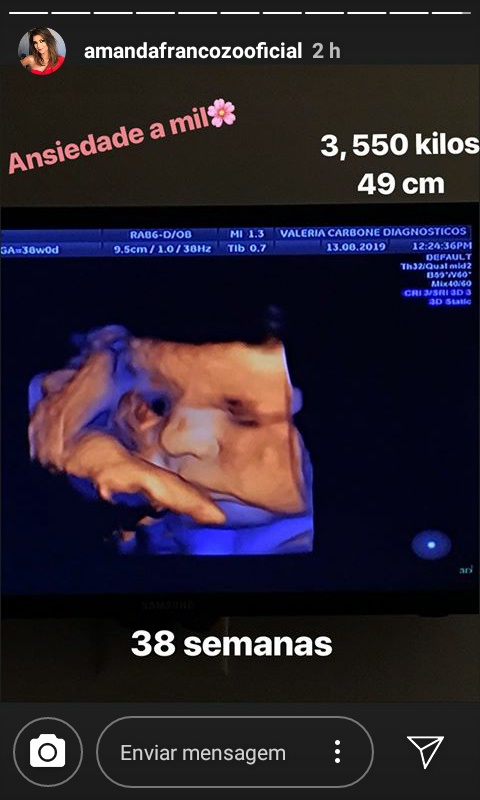

Nesta terça-feira (13), a apresentadora usou as redes sociais para compartilhar com os seus fãs, a sua visita ao médico, ela aproveitou para explicar os cuidados que se deve ter, e mostrar o ultrassom da sua pequena com 38 semanas.

“Estou aqui na Doutora Valéria Carbone porque hoje eu completo 38 semanas né Val? ela pergunta pra doutora, passou hein caramba vai dando aquele titititi no coração”, disse Amanda, ao compartilhar a imagem da filha.